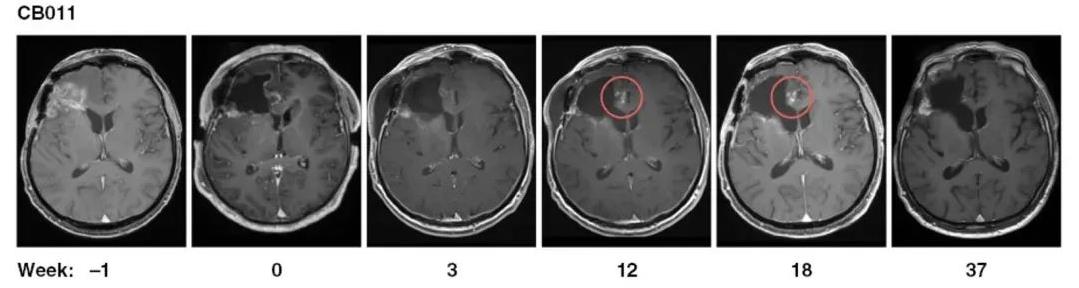

CAR-NK细胞治疗胶质母细胞瘤,中位总生存期长达135周

除了血液肿瘤外,CAR-NK细胞治疗多款实体瘤的潜力也不容小觑。《Neuro-Oncology(神经肿瘤学)》就曾报道过“CAR-NK细胞治疗复发性HER2阳性胶质母细胞瘤”的Ⅰ期惊艳结果。在本次研究中,入组9例复发性HER2阳性胶质母细胞瘤(GB)患者,这些患者在复发手术期间,在手术腔边缘进行CAR-NK细胞注射治疗,结果显示:

1、中位总生存期(OS):入组患者(n=9)中位总生存期(OS)达到31周。其中,出现假性进展的2例患者OS更长,分别达到98周、135周。

2、中位无进展生存期(PFS):9例患者中位无进展生存期(PFS)达7周。而出现假性进展的2例患者PFS更是长达37周。

3、病情稳定(SD):56%的患者(5例)在复发手术和持续7~37周的CAR-NK治疗后,达到病情稳定(SD)。

值得一提的是,治疗期间2例患者注射部位发现假性进展,提示存在治疗诱导的免疫反应。其中,MRI显示CAR-NK注射后第12周,患者切除边缘附近,出现斑点状对比增强,并在接下来的几周内消失,这可能与诱导的免疫反应相关,无需进一步治疗(详见下图)。

▲图源“Neuro-Oncology”,版权归原作者所有,如无意中侵犯了知识产权,请联系我们删除